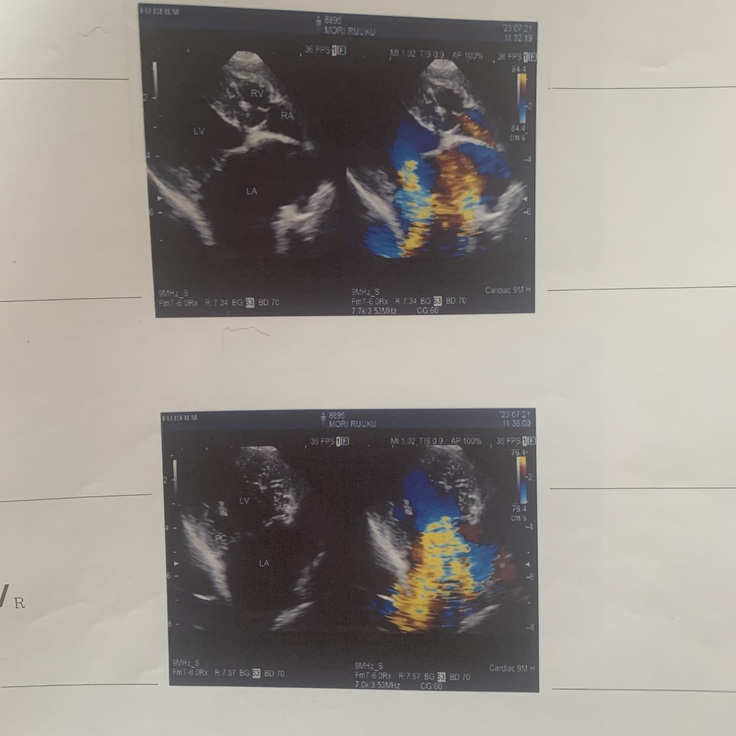

「僧帽弁閉鎖不全症」について

僧帽弁とは、左側の左心房と左心室の間にある弁のことです。通僧帽弁の働きにより左心房から左心室への一方向にしか血液は流れませんが、僧帽弁閉鎖不全症では、弁がうまく閉まらなくなることで逆方向の血流が認められるようになります。心臓が大きくなると、心臓だけでなく肺にも血液が溜まり、肺水腫と呼ばれる状態になります。肺水腫になると水中で溺れているのと同じような状態になり、呼吸が苦しくなります。僧帽弁閉鎖不全症の病状が進行すると、呼吸が苦しくなったり、腎不全などを併発して最終的には死に至る可能性があります。

その後、また呼吸が苦しそうで一度酸素室に2日ほど入院しました。そして、僧帽弁閉鎖不全症手術の名医がいる病院を紹介され、そこで検査を受けてきた次第(7/21)です。

重症と診断され、手術は8月中に受けられる見込みとなりました。

手術を行う病院での検査(7/21)以降、自宅で安静にしていますが、心臓が肥大していることから出る咳が頻発すること、僧帽弁閉鎖不全症後期である泡のような嘔吐の症状があるため、通院/検査をしながら日々を送っております。